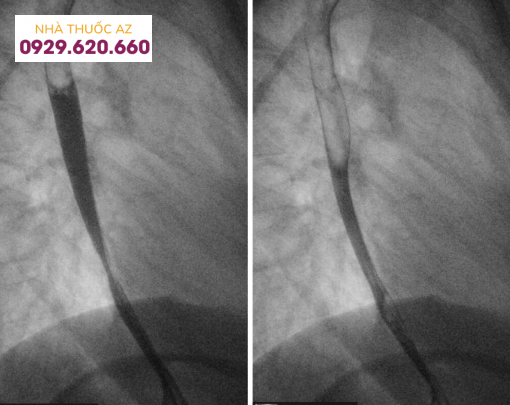

Đối với hẹp thực quản, theo một nghiên cứu được thực hiện trên bệnh nhân thực quản do bạch cầu ái toan, tỉ lệ phát hiện được hẹp bằng chụp Baryt lên đến 71% trong đó chủ yếu là hẹp ở đoạn dưới thực quản. Một nghiên cứu khác ghi nhận đoạn hẹp chủ yếu nằm ở phía trên hoặc thực quản đoạn ngực.

Đường kính của đoạn hẹp trung bình khoảng 1cm và vị trí hẹp ở phía đoạn thực quản trên/giữa có xu hướng dài hơn so với đoạn dưới. Tùy vị trí đoạn hẹp trên chụp Baryt vẫn cần cân nhắc đến các chẩn đoán phân biệt khác. Các nguyên nhân khác gây hẹp ở đoạn thực quản trên hoặc giữa bao gồm thực quản Barrett, xạ trị vùng trung thất, sử dụng một số loại thuốc như NSAID, quinidine, trong khi hẹp ở đoạn dưới thực quản có thể do viêmthực quản trào ngược. Cần chú ý những bệnh nhân có hình ảnh hẹp thực quản trên chụp Baryt thường có triệu chứng nuốt khó và đây chỉ là một dấu hiệu gợi ý, cần kết hợp nhiều yếu tố liên quan đến bệnh sử, triệu chứng lâm sàng, hình ảnh nội soi và mô bệnh học.Vòng thực quản cũng là hình ảnh hay gặp với nhiều thuật ngữ được sử dụng như “khí quản hóa thực quản” hay “thực quản dạng vòng”. Vị trí và sự phân bố của các vòng thực quản rất khác nhau trên nội soi, có thể ở các đoạn của thực quản hoặc phân bổ lan tỏa nhiều chỗ. Đôi khi những vòng này có thể gây hẹp khiến dây sợi khó đưa qua được. Trên chụp Baryt, các vòng này thường nhiều, hay xuất hiện gần nhau, có dạng đồng tâm dọc theo lòng thực quản.

Hình 10: Hình ảnh hẹp thực quản do Herpes ở bệnh nhân suy giảm miễn dịch mặc phải (Nguồn: radiologykey.com)

Hình 11: Hẹp thực quản do viêm thực quản sau xạ trị (Nguồn: radiologykey.com)

Hình 12: Hẹp thực quản do viêm thực quản trào ngược (Nguồn: radiologykey.com)